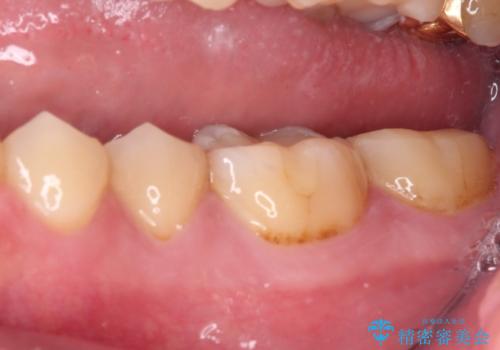

- 左右下顎の奥歯に違和感を感じるとのことで来院された患者様です。

最近ものが挟まりやすくなったり、冷たいものがしみるようになったりと言った症状があり、診査したところ、歯質の欠損や不適修復物などが認められました。

精度の高いセラミックインレーによる修復治療が第一選択となりますが、一方の歯は元々修復物が大きく、咬合力の強い方であったので、セラミッククラウンによる補綴治療を行うこととしました。